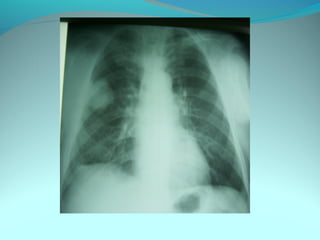

Cliché normal